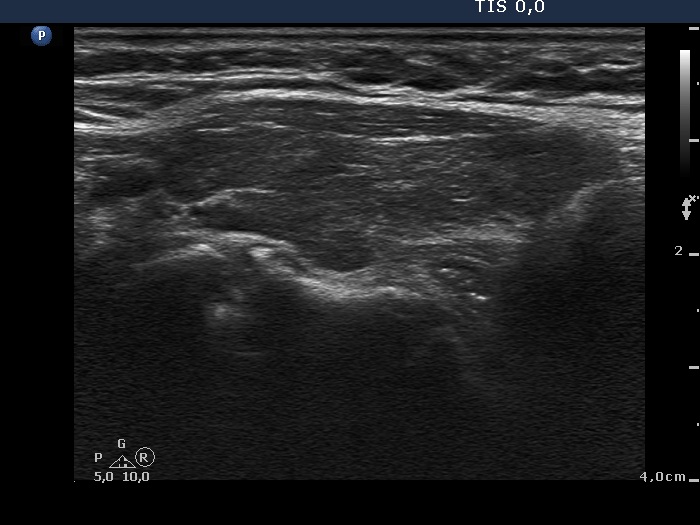

Consecutively operated patients with autoimmune thyroid disease - case 9 (1681) (ultrasonographic picture 5)

The patient is in hyperthyroid state

Left lobe, longitudinal scan. The discrete areas do not correspond to pathological nodules.